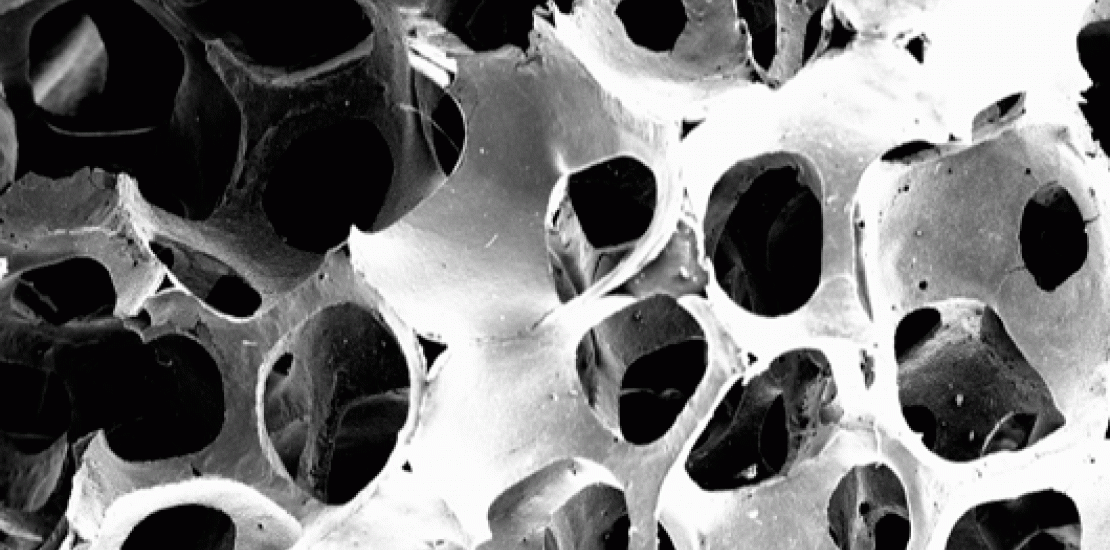

Partículas de colágeno

Estos investigadores ha conseguido incorporar, por primera vez esta sustancia, conocida por sus propiedades elásticas en la piel, a los agentes encargados de la formación y composición del hueso, HA (estructura del hueso) y BTCP (formador del hueso), lo cual supone una revolución en la regeneración y aumento de densidad de la estructura ósea.

Los resultados de incorporar esta proteína a las células óseas creadas en el laboratorio (biomaterial) se traduce en una cicatrización más rápida y una mejora significativa en la recuperación de intervenciones odontológicas, principalmente, en pacientes que presentan signos de osteoporosis